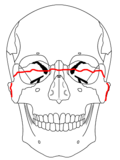

- Le Fort II fracture (pyramidal) may result from a blow to the lower or mid maxilla. The key component of these fractures beyond the pterygoid plate fractures is involvement of inferior orbital rim. When viewed from the front, the fracture is classically shaped like a pyramid. It extends from the nasal bridge at or below the nasofrontal suture through the superior medial wall of the maxilla, inferolaterally through the lacrimal bones which contain the tear ducts, and inferior orbital floor through or near the infraorbital foramen.

- Le Fort III fracture (transverse), otherwise known as craniofacial dissociation, may follow impact to the nasal bridge or upper maxilla. The salient feature of these fractures, beyond pterygoid plate involvement, is that they invariably involve the zygomatic arch, or cheek bone. These fractures begin at the nasofrontal and frontomaxillary sutures and extend posteriorly along the medial wall of the orbit, through the nasolacrimal groove and ethmoid air cells. The sphenoid is thickened posteriorly, limiting fracture extension into the optic canal. Instead, the fracture continues along the orbital floor and infraorbital fissure, continuing through the lateral orbital wall to the zygomaticofrontal junction and zygomatic arch. Within the nose, the fracture extends through the base of the perpendicular plate of the ethmoid air cells, the vomer, which are both part of the nasal septum. As with the other fractures, it also involves the junction of the pterygoids with the maxillary sinuses. CSF rhinorrhea, or leakage of the nutrient laden fluid that bathes the brain, is more commonly seen with these injuries due to ethmoid air cell disruption, as the air cells are located immediately beneath the skull base.[4]